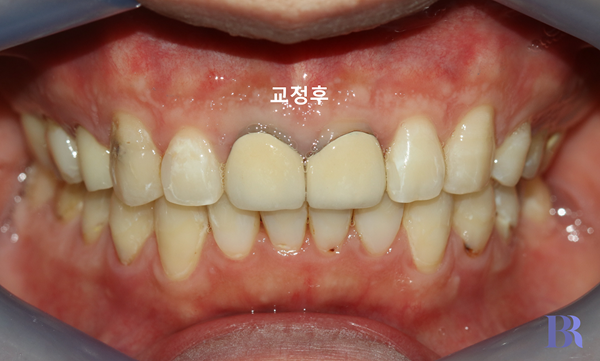

교정 후 입안 정면 모습

윗니가 아랫니를 깊게 덮는 것이

완벽히 해소가 되었습니다.

그렇기 때문에

윗니를 발치한 공간이

충분히 입술이 들어가는데

사용될 수 있었습니다.